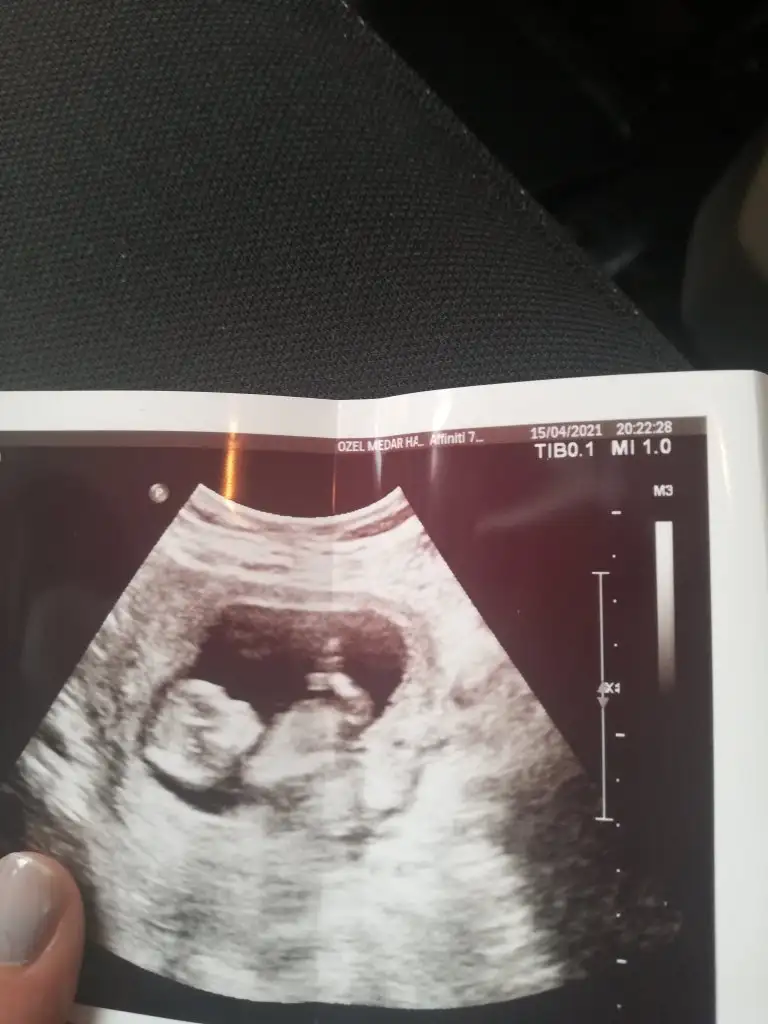

Kızlar selamlar, rica etsem bizim için de tahminde bulunur musunuz? Çok çok teşekkür ederim 💖😊

Tahminde bulunurmusun